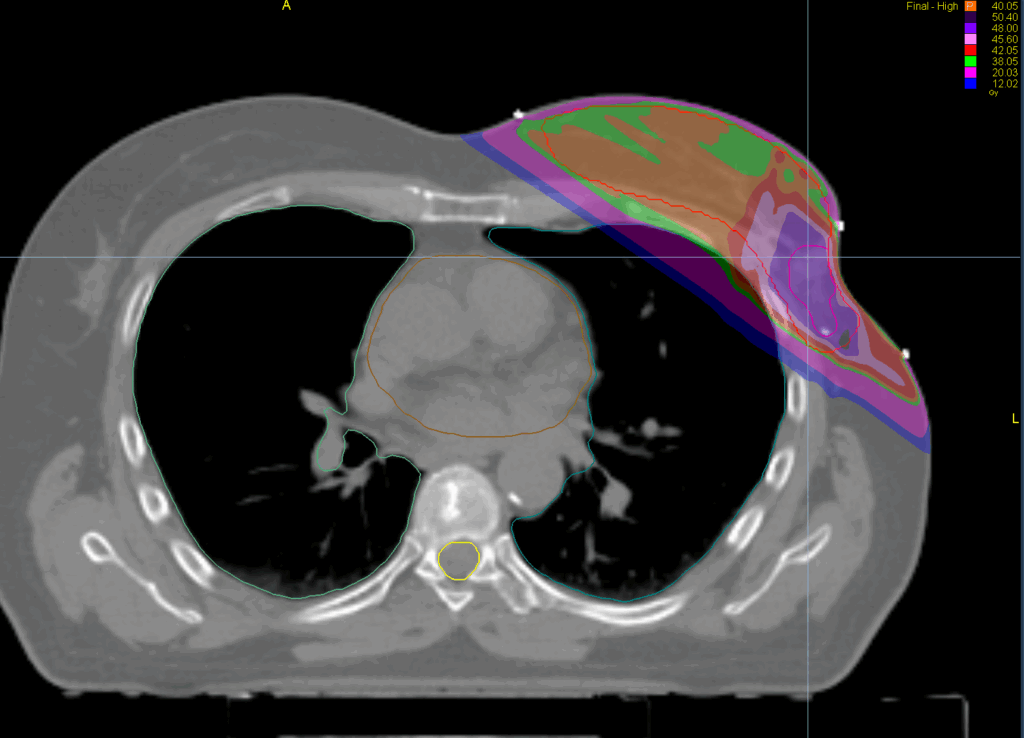

Treatment Plan Images

Fractionation / Protocol Used

40 Gy in 15 fractions

Mode

- TomoDirect™ 5 angles

- TomoEDGE™ 5 cm